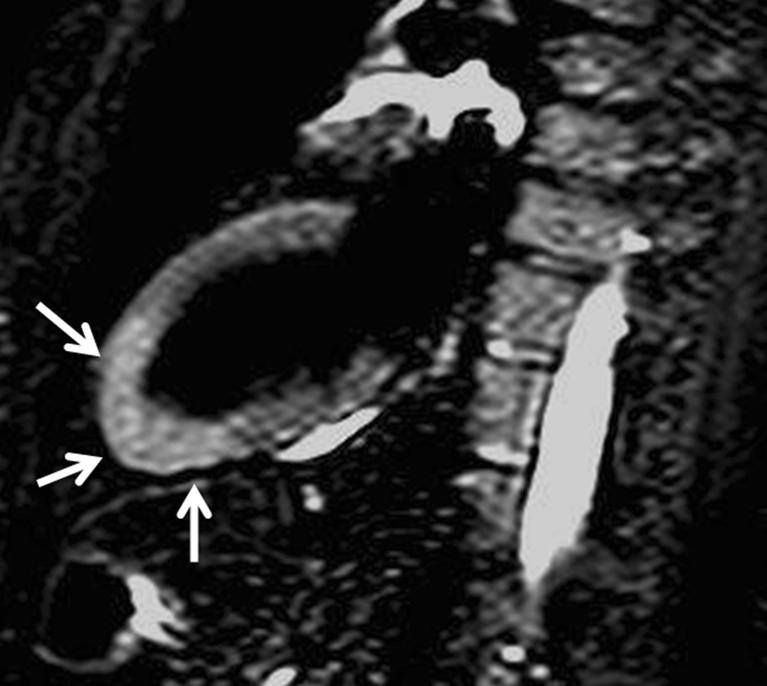

Left ventricular apical diseases.

There are many disorders that may involve the left ventricular (LV) apex; however, they are sometimes difficult to differentiate. In this setting cardiac imaging methods can provide the clue to obtaining the diagnosis. The purpose of this review is to illustrate the spectrum of diseases that most frequently affect the apex of the LV including Tako-Tsubo cardiomyopathy, LV aneurysms and pseudoaneurysms, apical diverticula, apical ventricular remodelling, apical hypertrophic cardiomyopathy, LV non-compaction, arrhythmogenic right ventricular dysplasia with LV involvement and LV false tendons, with an emphasis on the diagnostic criteria and imaging features. ELECTRONIC SUPPLEMENTARY MATERIAL: The online version of this article (doi:10.1007/s13244-011-0091-6) contains supplementary material, which is available to authorized users.